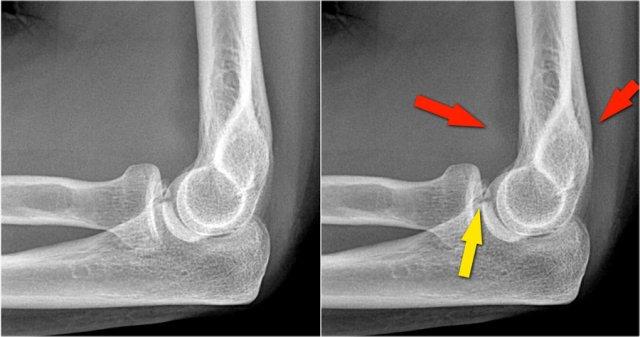

Đây là hình ảnh chụp X-quang tư thế nghiêng của khuỷu tay một bệnh nhân bị ngã chống tay duỗi thẳng.

Hình ảnh X-quang cho thấy tràn dịch khớp (mũi tên đỏ) và gãy mỏm vẹt (mũi tên vàng).

Continue with the MR-images.

Đây là hình ảnh MRI.

Hãy xem các hình ảnh và sau đó tiếp tục đọc…

Coronal view:

- Dây chằng bên ngoài bị bóc tách hoàn toàn (mũi tên vàng).

- radial head is subluxed.

- phù tủy xương của mỏm vẹt do gãy xương (mũi tên đỏ).

Sagittal view:

- Chỏm xương quay bị bán trật nhẹ ra phía sau (mũi tên vàng).

- Large effusion and capsular disruption posteriorly.

- Đụng dập mặt sau của chỏm con do va chạm với mỏm vẹt (mũi tên đỏ).

All these signs are the result of a posterior dislocation.